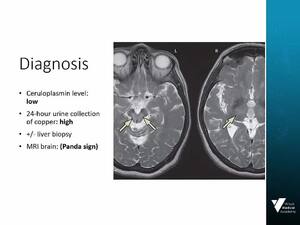

- Clarify the diagnosis and management of Wilson Disease